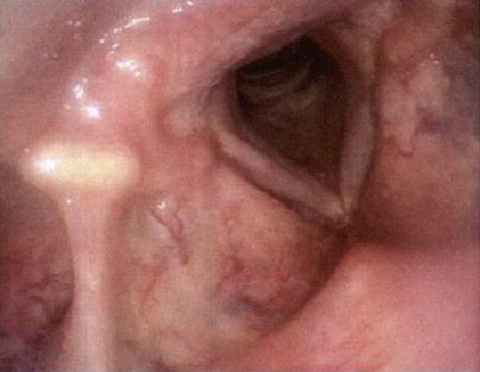

Postoperative

Four Month Follow-up

Postoperative

Nine Month Follow-up

Postoperative course was marked by gradual and significant improvement of voice production with no dysphagia or dyspnea. Fiberoptic Transnasal laryngoscopy on postoperative visit showed healthy healing of excision site with no signs of pathological inflammation. Four- and nine-month follow-ups, respectively, did not show any evidence of disease recurrence.